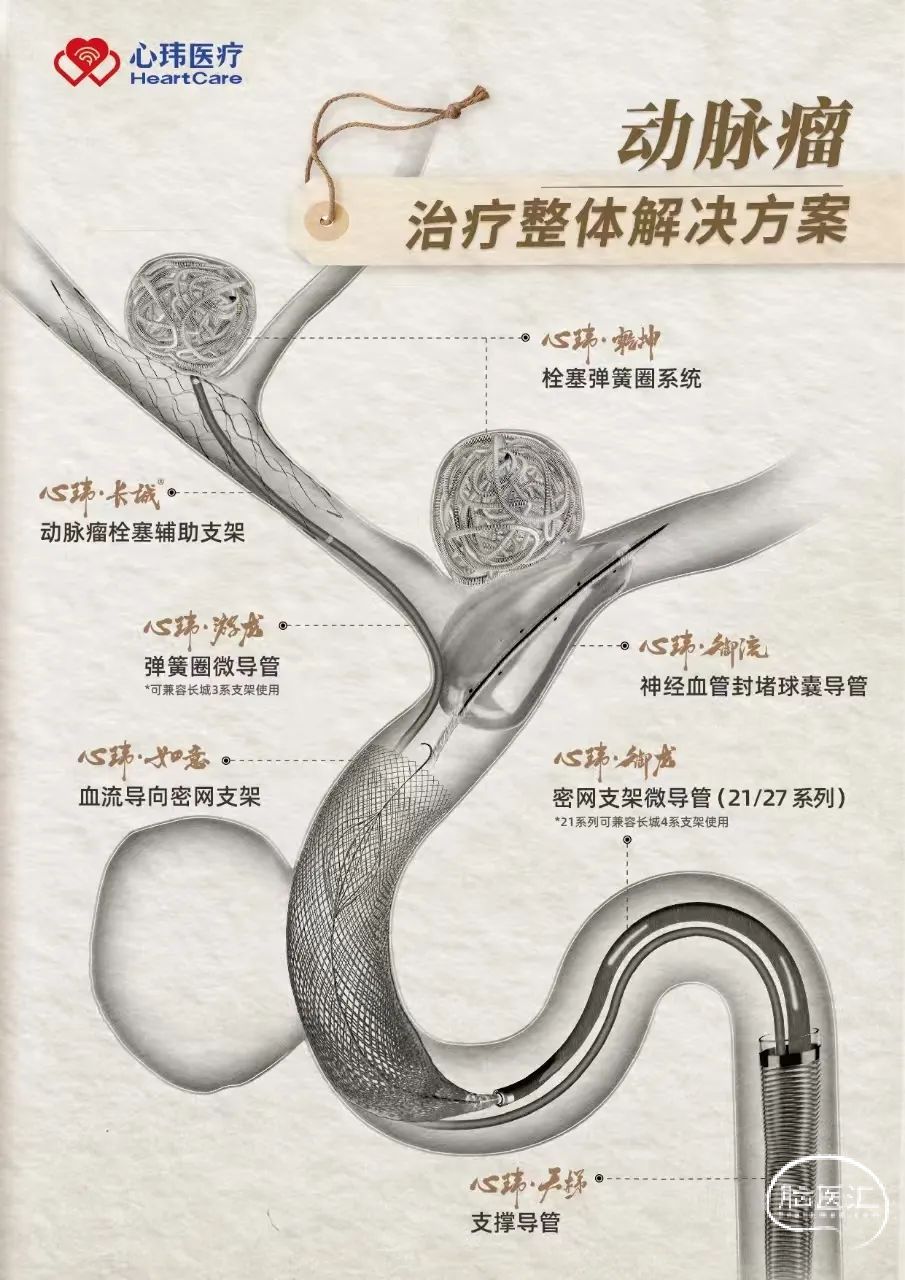

心玮,国产唯一提供动脉瘤治疗整体解决方案商